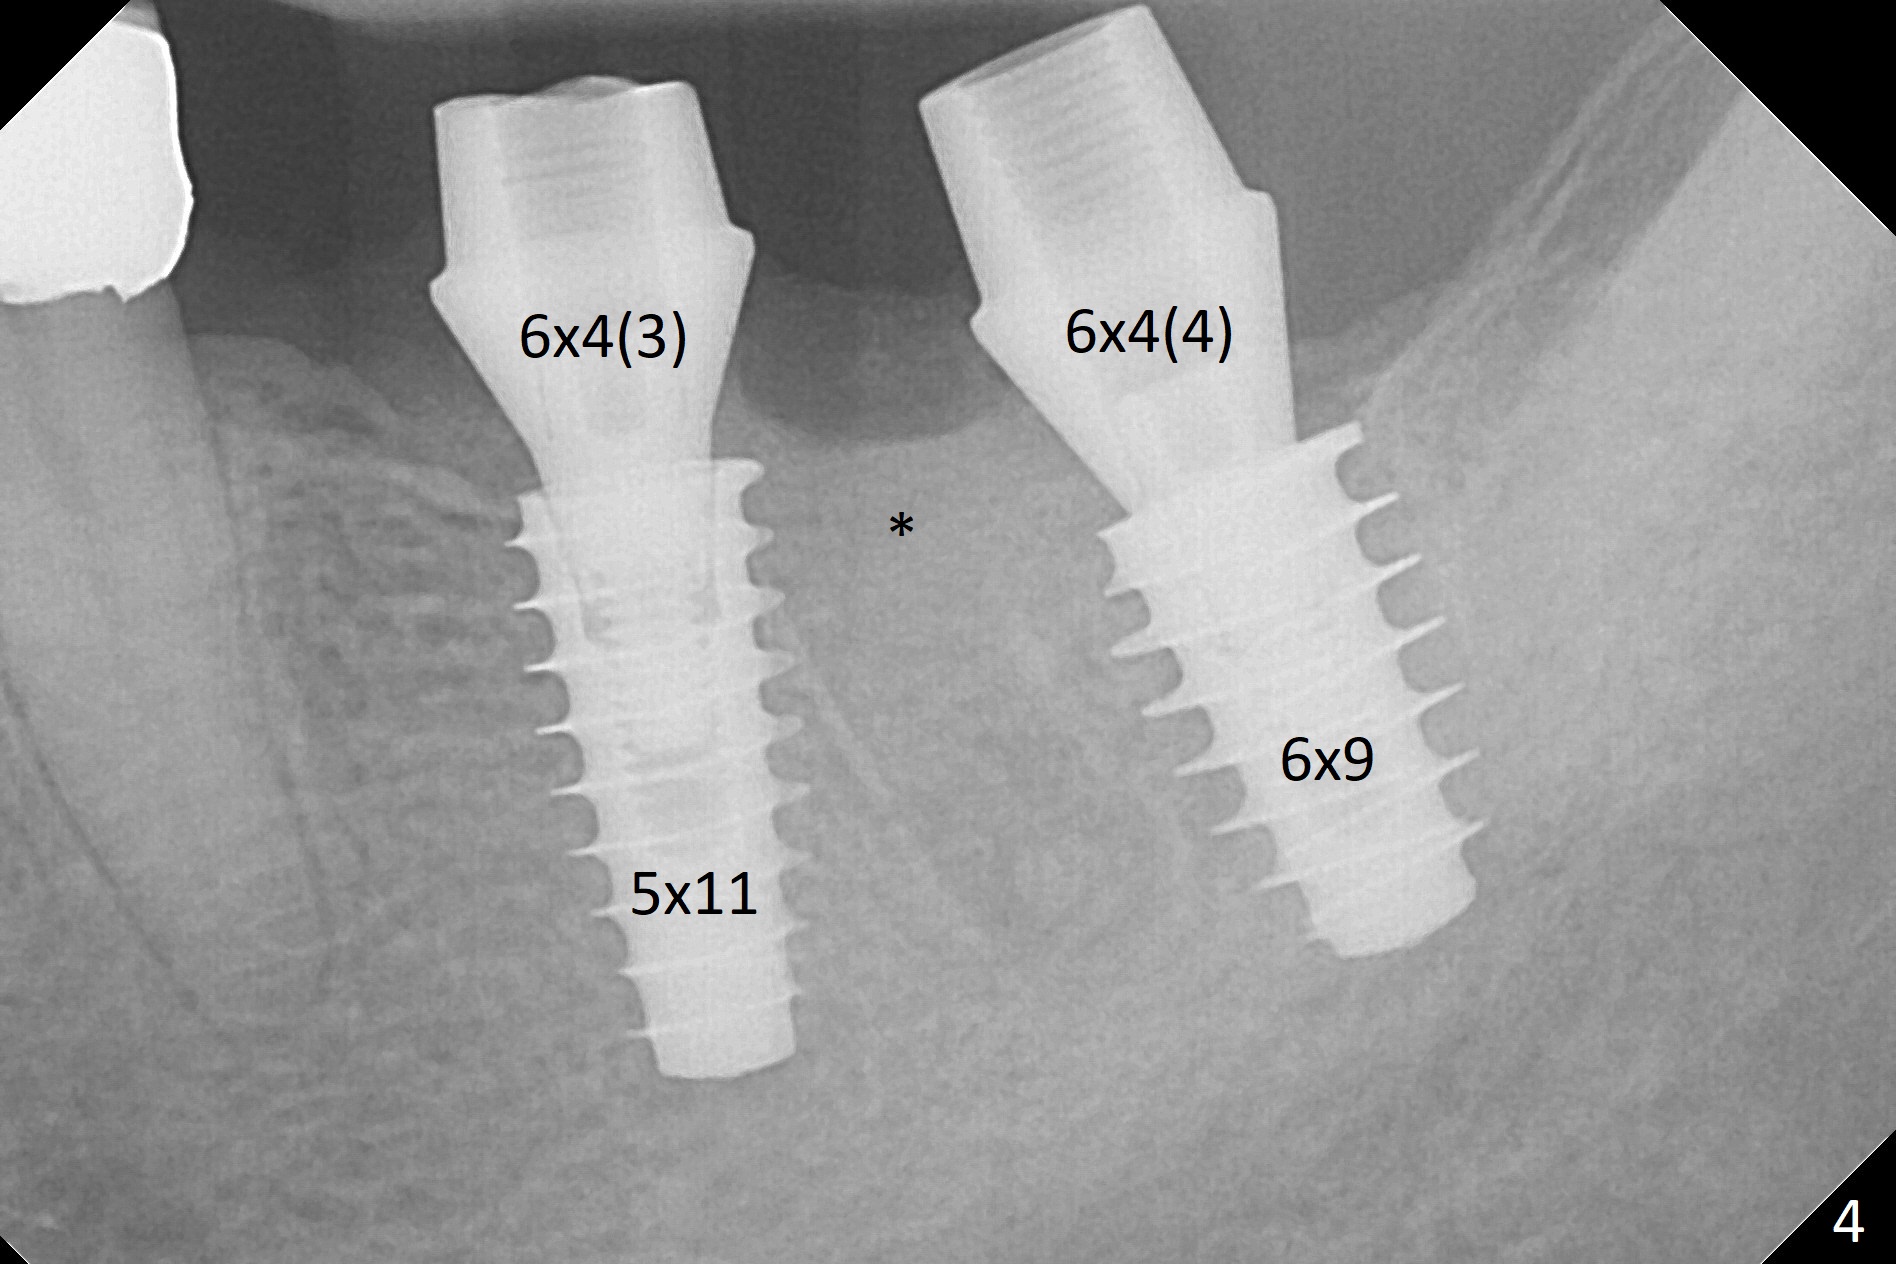

After extraction of the residual root at #18 (Fig.1), the septum is narrow, while the distal socket seems to be the most appropriate site for implant placement (Fig.2 (M: mesial)).  In fact the implant needs to tilt slightly distally (relative to the original trajectory of the distal socket, Fig.3 green) to occlude with the opposing tooth.  The implant at #19 could be placed more mesially (Fig.4 (*: Vera Graft)).

A drawback of placing an implant in the distal socket of the 2nd lower molar is closer to the Inferior Alveolar Canal.  The implants seem to have osteointegrated 4.5 months postop (Fig.5).  While the ridge at #19 appears to be wider than preop (as compared to Fig.1), that at #18 seems to be atrophic 5 months postop (Fig.6 * (1 week post cementation)).  The distal implant placement at #19 may increase possibility of abutment screw loosening during functioning (Fig.7 *).  When the patient returns for periodic exam 1.5 months post cementation, loose contact between the implant crowns is noted (Fig.8).  The bony trabeculae form between the 2 implants crestally 12 months postop, i.e., 7 months post cementation (Fig.9).  The loose contact between the 2 implants is corrected 14 months post cementation.